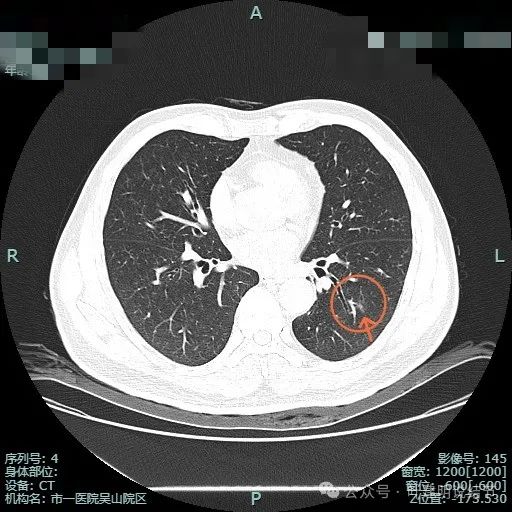

先看非薄层影像:

左上病灶出现,密度较淡,但轮廓较清。

密度不纯,有明显分叶。

有血管异常增粗与进入,边缘有细毛刺征。

血管穿行与表面浅分叶。